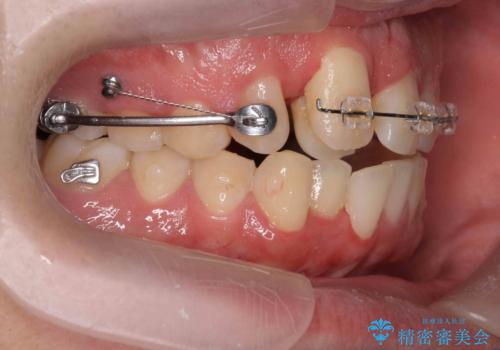

正中過剰埋伏歯で生じた前歯の審美障害 矯正治療での改善

- 前歯の見た目に悩まれて来院されました。

当初他院では、抜歯を行いセラミックブリッジを提案されていましたが、他の方法はないかと総合歯科治療を行う当院へと相談来院されました。

「時間がかかっても良いので、できれば歯を抜かずに矯正治療で治したい。」という強い希望があったので、矯正治療で歯並び・審美性の改善を計画します。

見た目、噛み合わせが大きく改善し、大変喜んでいただくことができました。